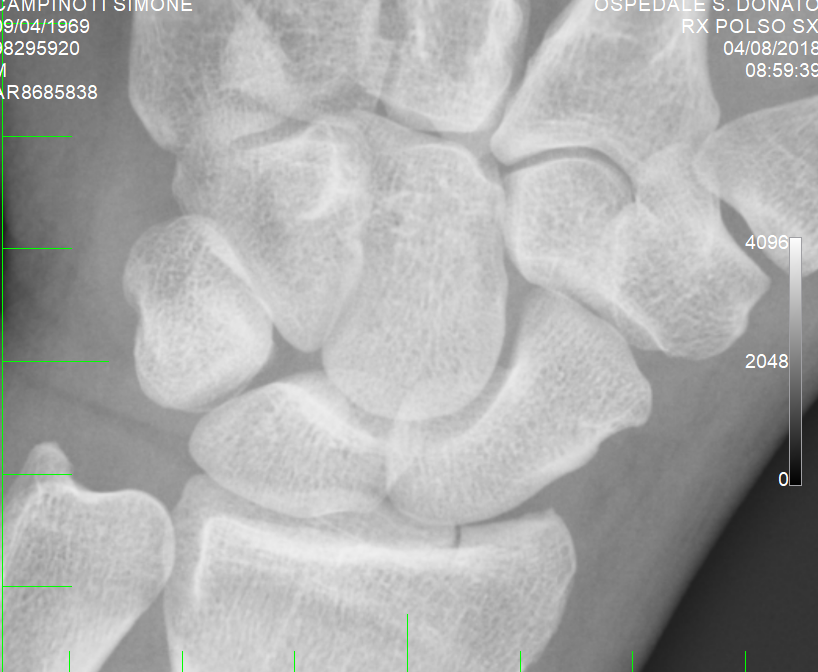

Ieri al pronto soccorso mi hanno diagnosticato frattura composta

articolare dell'epifisi distale del radio, allego immagini,

polso 2.PNG

[ 492.46 KiB | Osservato 833 volte ]